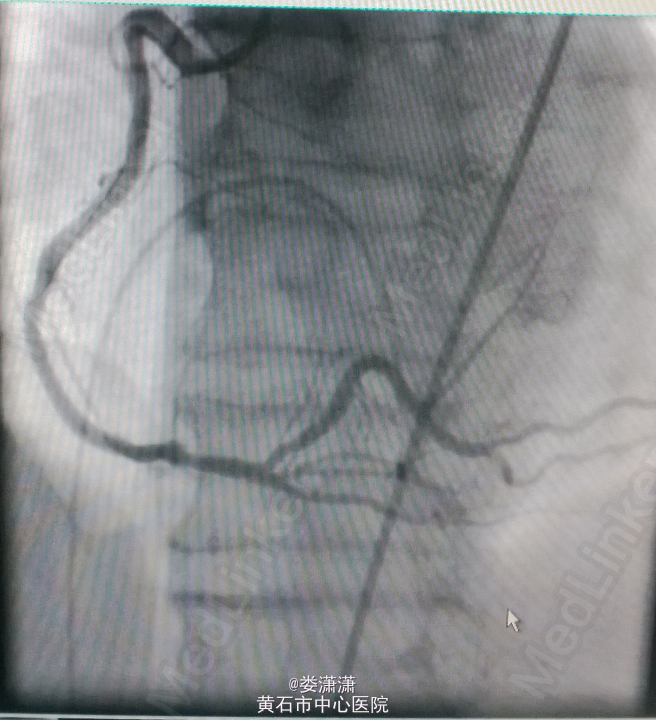

诊断:1.急性下壁心肌梗死(STEMI),心源性休克,心功能IV级(killip分级);2.高血压病2级(很高危);3.2型糖尿病;4.陈旧性脑梗塞;5.高尿酸血症。 处理——收入CCU后立即转去导管室行急诊冠脉造影术,术中见右冠中段以远全部闭塞,未见侧枝循环,前降支近中段见节段性狭窄70-80%,术中经6F Thrombuster血栓抽吸导管反复多次抽吸右冠,抽出数条红色血栓,并于右冠中段病变处植入Firebird 4.0*23mm药物支架,缝合鞘管时患者心电监护提示加速性实行逸博心律(110次/分左右),5min后突发室速、室颤,立即予床边电极除颤后转位室性逸博心律(105次/分)。返回病房后夜间患者多次出现室颤,予点击除颤、胺碘酮静滴等治疗后好转。术后24h内患者出现少尿,予静脉补液(5000ml/天左右)、利尿等,患者尿量基本维持在2000ml/天。术后辅查心电图见下壁导联ST段明显回落。余予抗血小板聚集、稳定斑块等治疗。